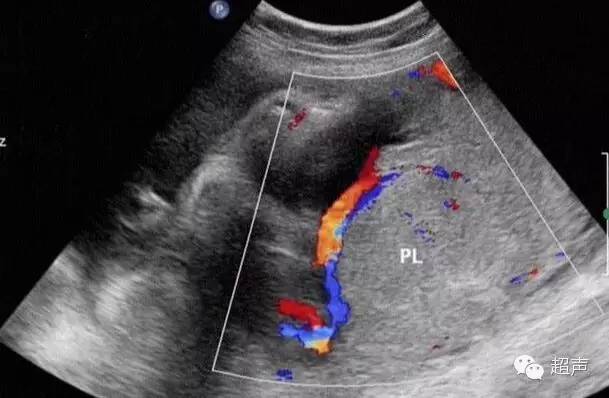

不过临床上还有一种常用且简便可靠的发现诊断帆状胎盘的方法,那就是彩色超声多普勒技术,随着超声技术的不断发展和广泛应用以及超声医师对帆状胎盘认识的提高,产前帆状胎盘的检出率逐年提高。

超声检查可以观察胎盘类型、位置、脐带附着于胎盘的部位,部分孕妇需经阴道超声检查的,还可以比较清楚的显示宫颈内口及其周围的结构、胎膜上前置血管的走行情况。

研究发现,产前超声有目的地观察胎盘脐带附着部位,可提高帆状胎盘的显示率,诊断准确率可达91%。但是超声作为一种有效的检查方式,亦存在许多的影响因素,如孕周过大或过小,羊水过少,胎盘位于后壁以及胎儿位置的干扰等,从而降低了检查的正确率。